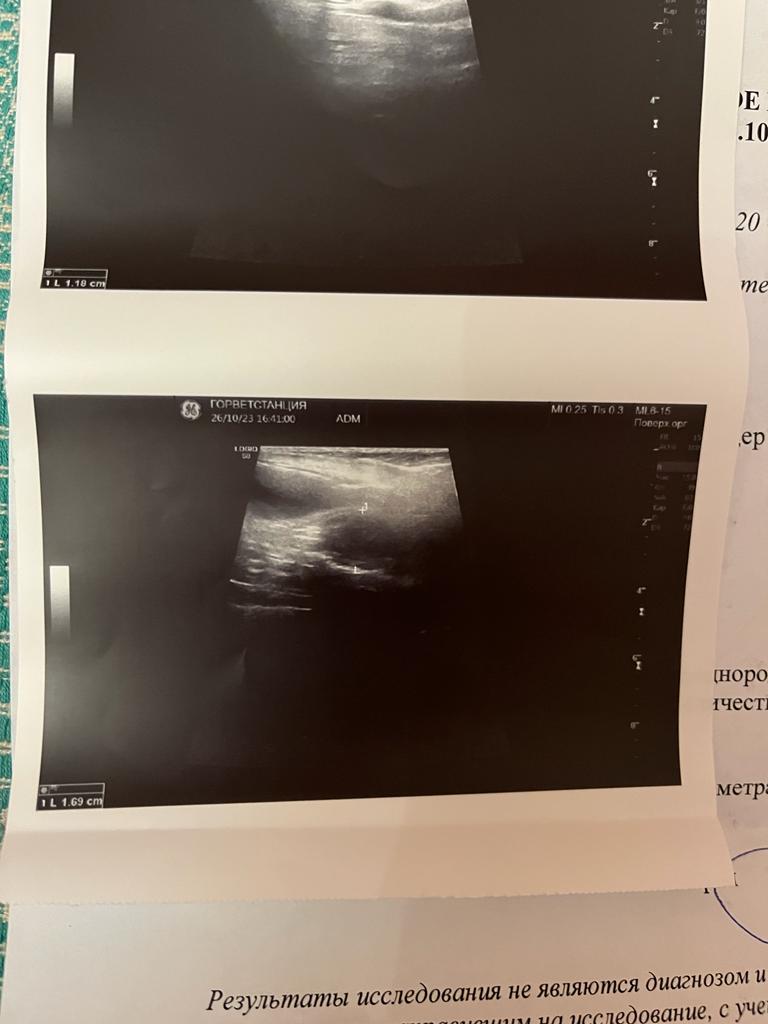

Спб, метис цверга Дара, 8-9 лет

Послеоперационная выписка